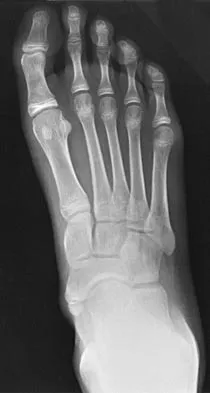

Figure 1 shows the radiograph of an 11-year-old boy who stubbed his great toe while playing soccer barefoot. He is able to walk home despite a small amount of bleeding at the nail fold. Management should consist of

Explanation

Great toe fractures through the physis should be considered open fractures if there is bleeding at the nail fold. Treatment should include irrigation and debridement and appropriate antibiotics. Immobilization with a cast is usually sufficient for treatment of the fracture. Noonan KJ, Saltzman CL, Dietz FR: Open physeal fractures of the distal phalanx of the great toe: A case report. J Bone Joint Surg Am 1994;76:122-125.